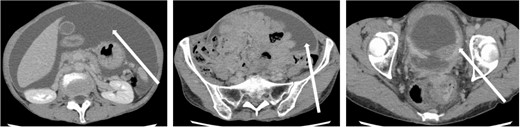

The patient was a 59-year-old female. She had undergone total mastectomy and axillary lymph node dissection for right breast cancer 23 years previously, and had undergone postoperative hormone therapy for 2 years. Computed tomography (CT) scan of the abdomen taken at the time of initial examination revealed significant ascites accumulation and some intestinal obstruction-like findings (Fig. 1). An ascites puncture was performed, and cytological examination of the ascites fluid showed a high N/C ratio and a nucleus that was adenocarcinoma in origin. The cell block was positive for BerEP4, CK7, GATA3 and mammaglobin; weakly positive for E-cadherin; and negative for CK20 and PAX8. IHC biomarker showed estrogen receptor (ER) (+), progesterone receptor (PR) (−) and HER2 (2+) (no amplification by FISH), and the diagnosis of luminal (non-HER2) type was made (Fig. 2). Based on these results, the patient was diagnosed with peritoneal metastasis from breast cancer.

CT findings. In addition to significant ascites accumulation, there was a partial bowel obstruction-like finding.